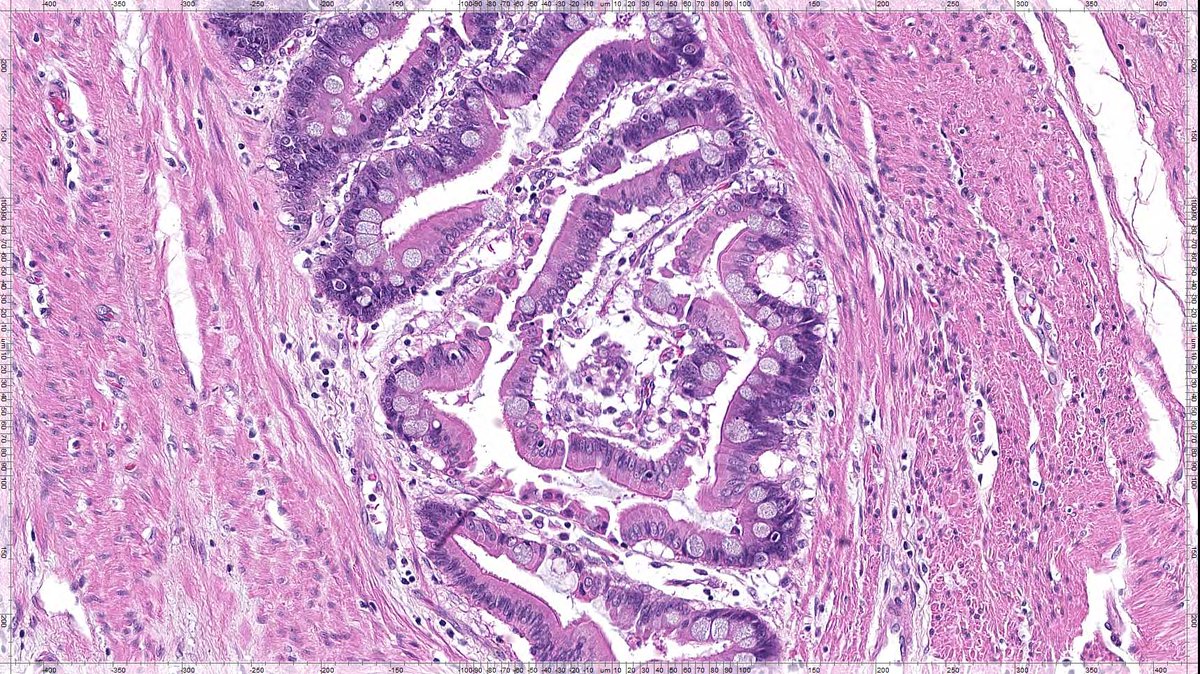

Here's an invasive tumor of the colon that I found this morning! This case is older than the majority of you - by a couple of decades! this one is special!! #GIpath